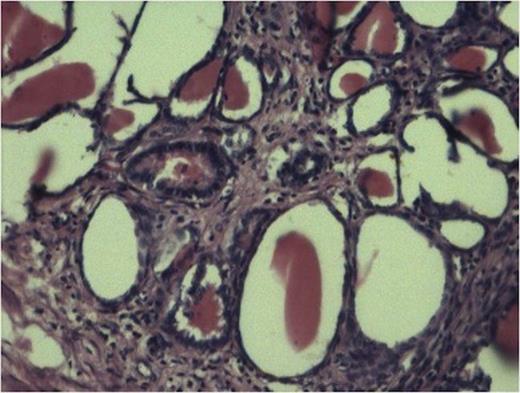

Histopathology from solid portions in pelvis region showed features of moderately differentiated squamous cell carcinoma (Fig 3). The tumor was not involving retroperitoneal soft tissue including renal vessels, Gerota’s fascia and lymph nodes.